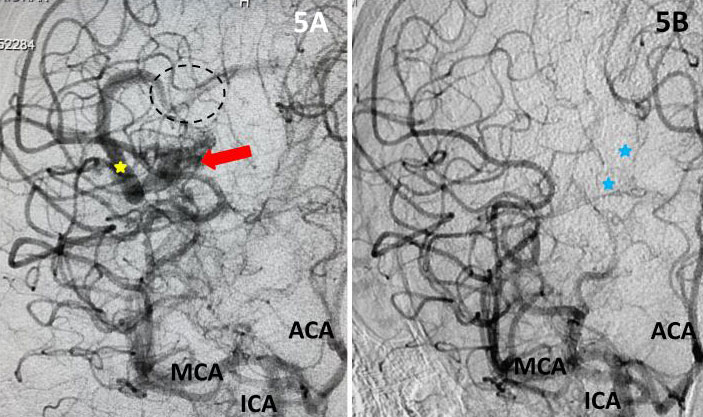

The patient was taken to the angio-suite where an angiogram confirmed a high flow, high pressure AVM fed primarily by the posterior cerebral artery with a small collateral from the middle cerebral artery (Fig 2 and 3). The AVM drained into a tortuous, partially occluded and stenotic single draining vein.

Fig 3. Lateral view, late-arterial phase of a right internal carotid artery (ICA) injection. Filling of the AMV (red arrow) by the fetal posterior cerebral artery (PCA) and small middle cerebral artery feeder (blue arrow). The large tortuous draining vein (yellow star) with venous stenosis and the suggestion of clot (dotted circle) can be seen.